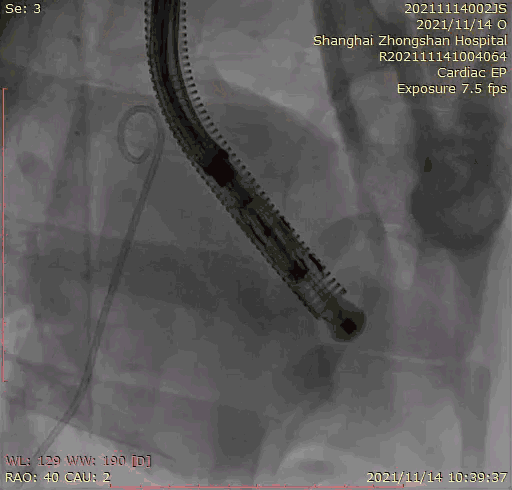

本次臨床前研究經(jīng)右側(cè)頸靜脈置入LuX-Valve Plus輸送系統(tǒng)可調(diào)彎鞘管,在DSA及超聲引導(dǎo)下將人工三尖瓣瓣膜植入到原有三尖瓣位置,利用獨(dú)特的錨定技術(shù)將人工瓣膜支架可靠固定在預(yù)定的位置。

上海中山醫(yī)院葛均波院士、錢菊英院長、周達(dá)新教授、潘文志教授、潘翠珍教授、李偉教授共同完成此次臨床前研究。術(shù)后葛均波院士對(duì)Lux-Valve Plus的器械操作性能給予了高度評(píng)價(jià),DSA和超聲影像也顯示出在本次研究中Lux-Valve Plus的安全性和有效性俱佳。